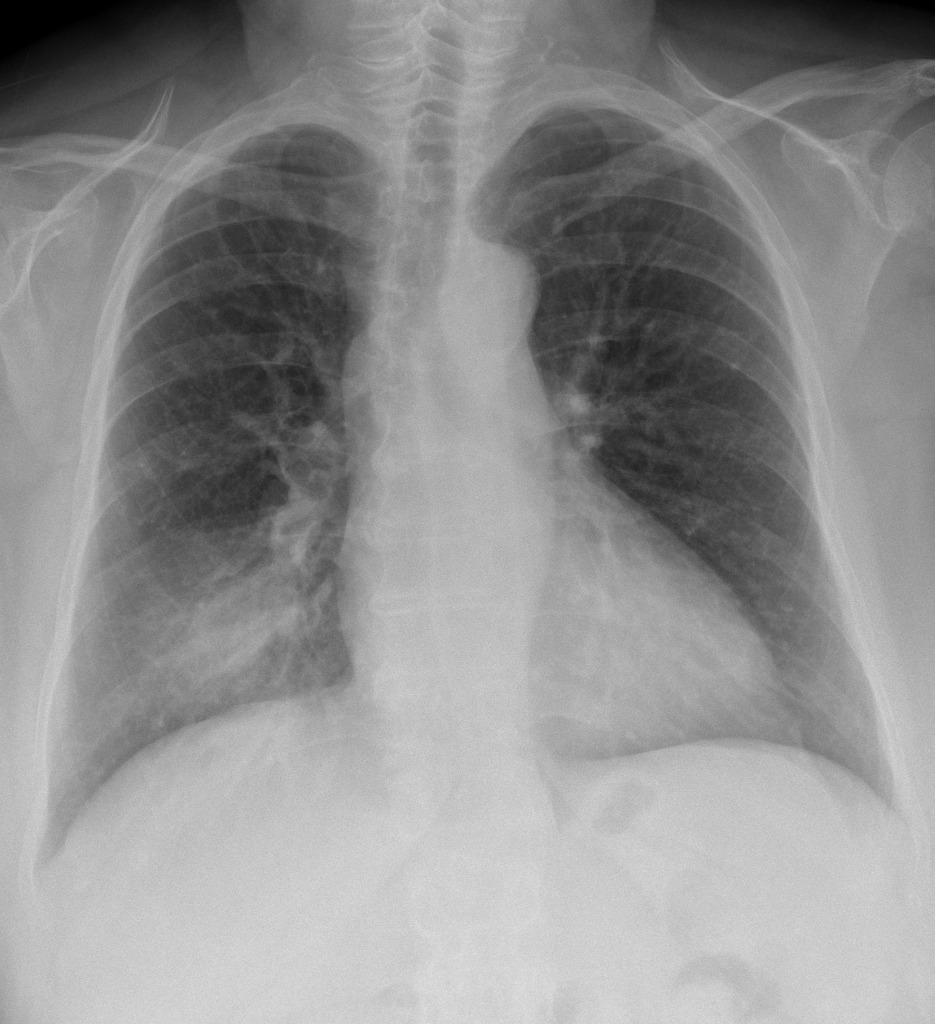

CXR for the case found here: